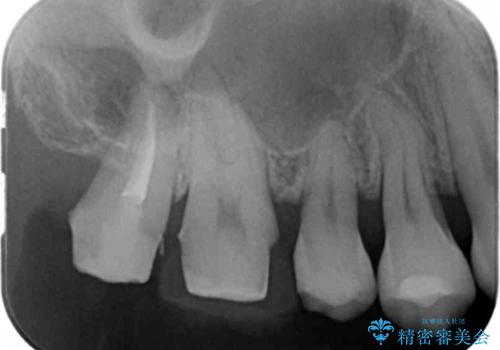

銀の詰め物を除去した後、その奥にある古い詰め物も除去し完全にむし歯を取り切ったことを確認してからセラミッククラウンを装着していきます。

- 右上67 仮歯+ジルコニアクラウン:11,000+110,000円 右上7/根管治療:保険 ファイバーコア:22,000円費用は治療当時の料金となります